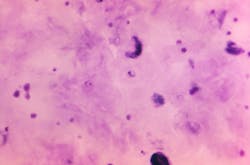

WHO’s latest World malaria report said there were an estimated 241 million malaria cases and 627,000 malaria deaths worldwide in 2020. This represents about 14 million more cases in 2020 compared to 2019, and 69 000 more deaths. Approximately two-thirds of these additional deaths (47,000) were linked to disruptions in the provision of malaria prevention, diagnosis and treatment during the pandemic.

Sub-Saharan Africa continues to carry the heaviest malaria burden, accounting for about 95% of all malaria cases and 96% of all deaths in 2020. About 80% of deaths in the region are among children under 5 years of age.